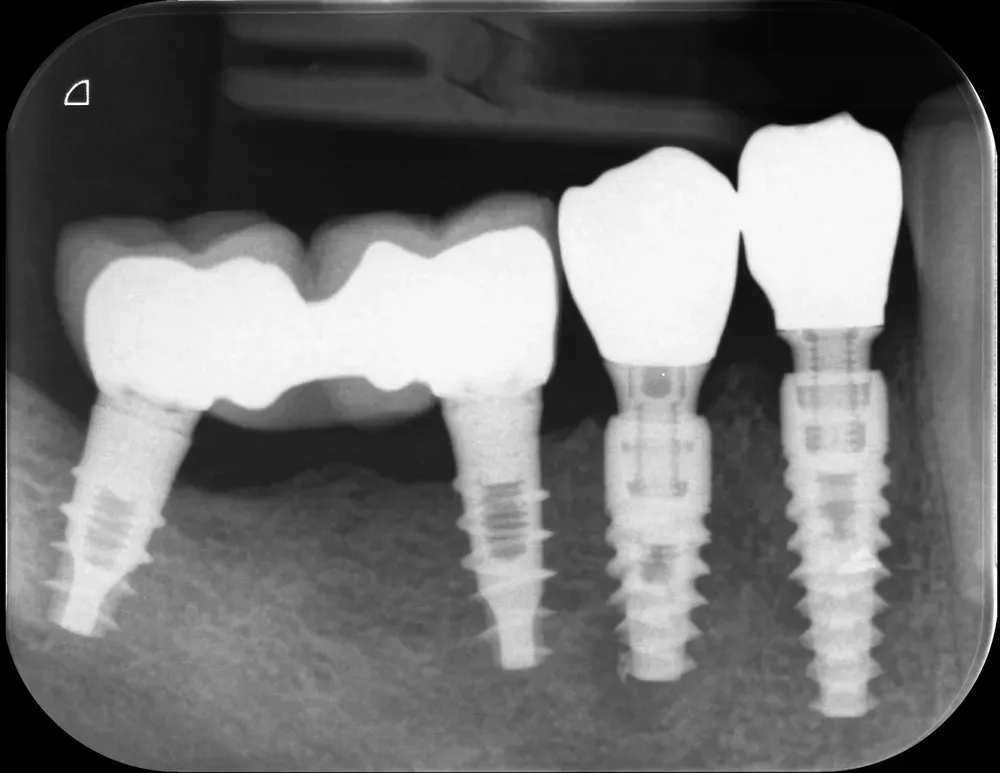

In questo caso, la stabilità primaria di entrambi gli impianti è stata eccellente, consentendo il posizionamento di una protesi provvisoria immediata. Utilizzando un approccio flapless “through-the-socket”, ho innestato il difetto buccale con un semplice xenoinnesto di osso eterologo. Questo è semplicemente il modo migliore per innestare: niente lembi se possibile.

La radiografia periapicale finale mostra il perfetto successo degli impianti e dell’innesto. Notare come il granuloma apicale del secondo premolare sia guarito perfettamente all’apice dell’impianto. Il granuloma non è stato rimosso. Infatti, nessun tessuto di granulazione deve mai essere rimosso (se non in presenza di purulenza e detriti non altrimenti rimovibili). È un retaggio di epoche lontane e di una visione “meccanicistica” della chirurgia orale ed è privo di fondamento scientifico.